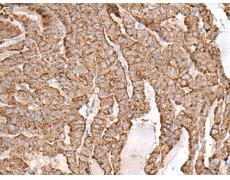

IHC positive control: |

Human thyroid cancer |